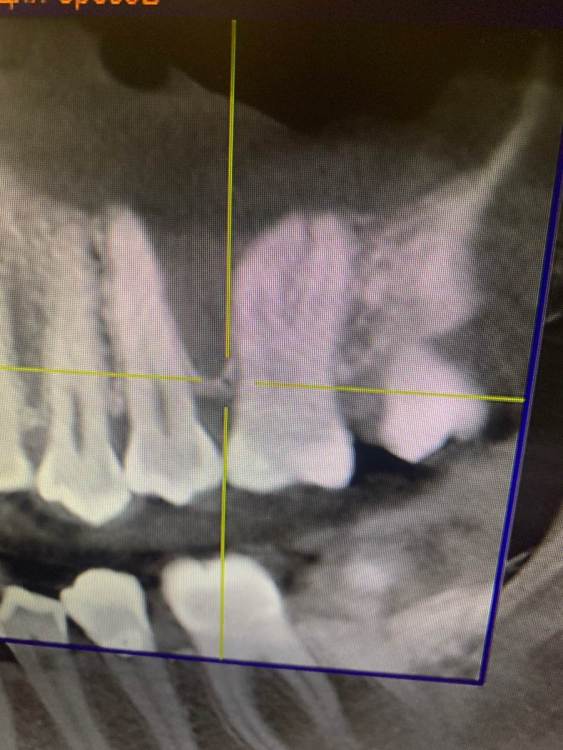

KOCTb Опубликовано 1 января, 2024 Поделиться Опубликовано 1 января, 2024 Здравствуйте коллеги. Может кто-то подскажет полезного. Пациентка. Лет 6 назад пришла с симптоматикой пульпита во втором секторе. На некоторых зубах были пломбы, без криминала. Зубы были проверены на витальность. Все живые. Пальпаторно передняя стенка ВП давала лёгкую чувствительность. Сделали КТ. Апикальных изменений не выявлено, а в пазухе слева признаки гайморита. Заполнена была бальше чем наполовину. Отправил к ЛОРу. Пролечили. Анатомическое строение не очень понравилось. С тех пор каждую зиму у неё обострение ВЧ синусита слева. Иногда даже два раза бывает. Каждый раз ЛОР в направляет к стоматологу и говорит, что гайморит одонтогенгый. Врачи рентгенологи в описании иногда там находят одонтогенгую кисту… Года два назад пациентка сходила поменяла все пломбы, на всякий пожарный. Со слов зубы все были витальные при лечении. Ну и собсвенно опять ВЧ синусит. Смущает анатомическое строение между 25 и 26 зубом. Не может ли там через периодонтальную щель «сифонить» ? Говорит между зубами иногда какой-то дополнительный дискомфорт есть. Ссылка на комментарий

Irouil Опубликовано 3 января, 2024 Поделиться Опубликовано 3 января, 2024 Было бы чему "сифонить" - зондировался бы свищ через пародонт, было бы разрушение межзубной перегородки. Имхо, это невозможно Одонтогенную причину пока в упор не вижу Ссылка на комментарий

KOCTb Опубликовано 15 января, 2024 Автор Поделиться Опубликовано 15 января, 2024 19 часов назад, Astronaft сказал: Здравствуйте. 6 лет назад: подробнее про симптомы пульпита? как полечили гайморит и чего добились? Анатомия действительно интересная. Интуитивно, или естественная впадина которая способствует застою либо проблемы в соустье вызывают застой и кислотный секрет лизирует самое слабое место. Опять же интуитивно, пациентке приказать зубы не трогать, не ходить выискивать проблемы. Очень подробно расспросить анамнез, в том числе что помогает, что запускает синусит. Если соустье открыто то я бы рекомендовал регулярно промывать физраствором с ЭДТА и выждать. Здравствуйте. Ну как обычно пульпитная симптоматика при ВЧ синусите. Разлитые периодические боли в верхнем секторе, с непонятной локализацией. Пальпаторно передняя стенка ВЧ пазухи давала болезненность. От 25 до 27 зуба. На КТ зубов затенение в ВЧ пазухе. Отправил тогда к ЛОРу. Подробности лечения у ЛОР врача тогда не знаю. Синуситы в холодное время года. Соустье пародонтальным зондом не выявлено. Носо-ротовая проба также отрицательная. Но тут и понятно если и есть ход, то крайне мизерный. Там слизистой завалено всё. Ссылка на комментарий